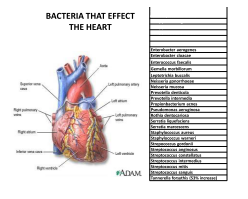

Though home for many bacterium

to surgery they don’t have to succumb

I dream that dentistry will finally discover

hundreds of microbes living under cover

Heart disease and even cancer

are not a normal healthy answer

And those pathological microbes fill our bodies

every organ providing lobbies

With invitations to move right in

this indeed is a biological sin